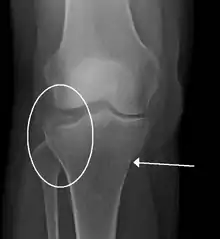

- Tibial plateau fracture

- Bumper fracture - a fracture of the lateral tibial plateau caused by a forced valgus applied to the knee

- Segond fracture - an avulsion fracture of the lateral tibial condyle